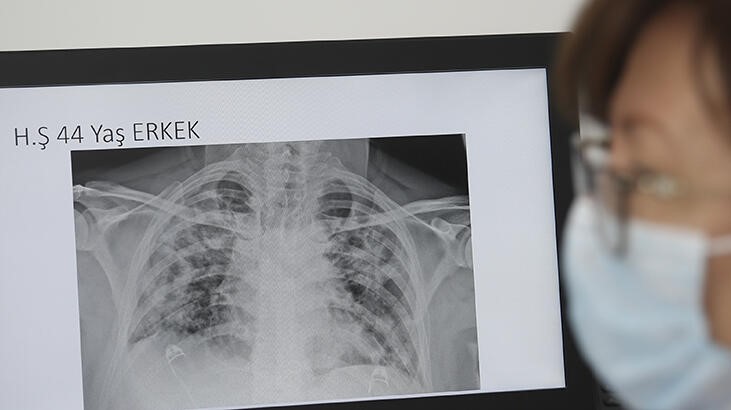

BBC'de yer alan habere göre, Oxford Üniversitesinden bilim insanları, yaşları 19 ila 69 arasında değişen 10 hastanın akciğerlerini ksenon gazı kullanarak manyetik rezonans (MR) ile taradı.

Tarama esnasında ksenon gazını içine çeken hastalardan 8'i nefes darlığı çektiğini söylerken, akciğer hasarının işaretleri görüldü.

Uzmanlar, hastalarda görülen akciğer hasarının, geleneksel tarama yöntemleri ile tespit edilemediğini belirtti.